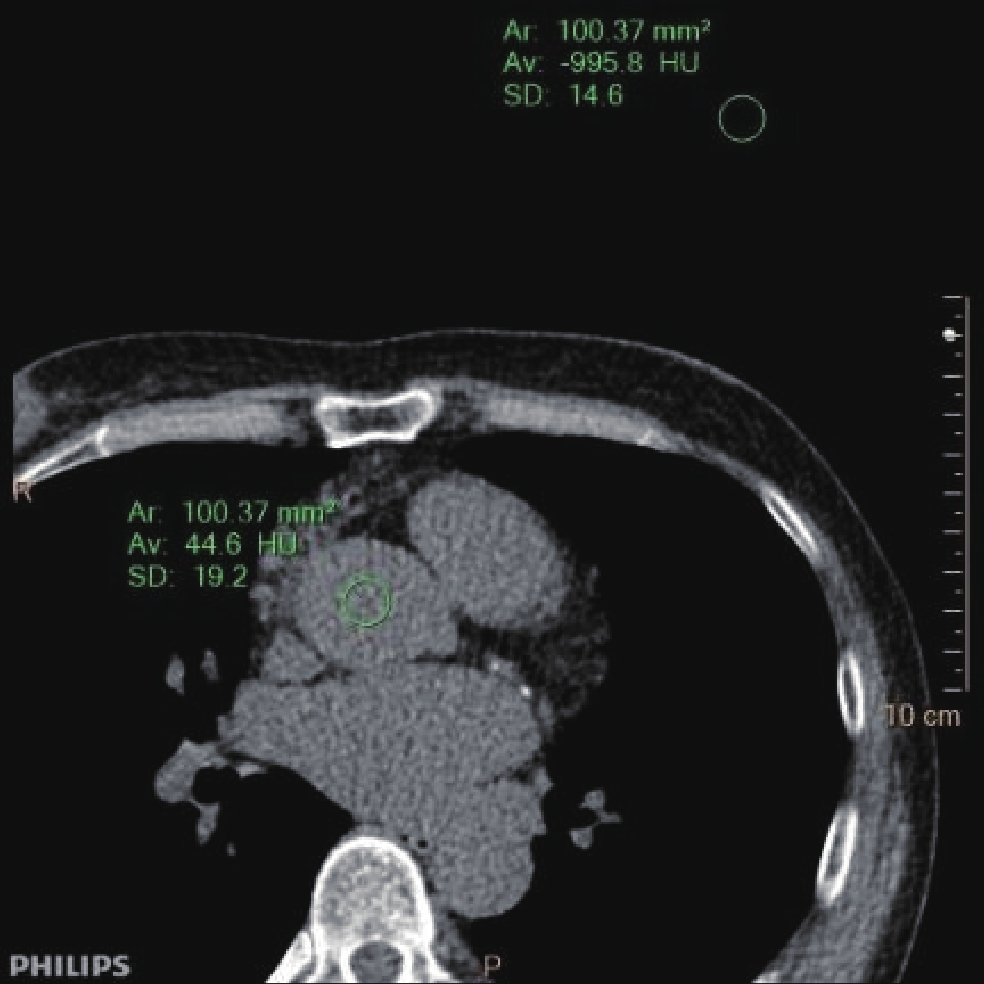

• 摘要: 目的:探讨智能最佳管电压技术SEMI模式(Care kV SEMI)联合迭代算法在冠状动脉检查中钙化积分低剂量扫描成像中的可行性。方法:模体实验采用Care kV SEMI模式和管电流调制技术(CareDose 4D on)。参数设置:SEMI 120 kV(ref.kV分别为100 kV、120 kV),ref.mAs分别为40、60和80 mAs,重建算法分别为滤波反投影算法(FBP)、基于模型的高级迭代算法(ADMIRE)3、4、5。比较各组图像的容积CT剂量指数(CTDIvol)、对比噪声比(CNR)和品质因子(FOM)。回顾性分析30例冠状动脉钙化积分扫描图像作为对照组(ref.kV 120 kV,ref.mAs 80 mAs,重建滤波反投影(FBP)算法),前瞻性采集109例患者冠脉钙化积分CT图像作为实验组(ref.kV 100 kV,ref.mAs 80 mAs,重建算法分别为FBP、ADMIRE 3、5),两组实际管电压均为SEMI 120 kV。记录并计算剂量长度乘积(DLP)、有效剂量(ED)、左主干(LM)和右冠状动脉(RCA)开口层面的CNR、钙化积分(Agatston Score)以及风险分级。由两名高年资诊断医生对患者冠脉图像进行4分法主观评价。对临床研究两组患者冠状动脉CT钙化积分扫描的辐射剂量、钙化积分数值、风险分级以及图像质量差异进行统计学分析。结果:①模体研究结果:实验组辐射剂量较对照组均降低;相同扫描条件CNR 随迭代算法等级增加而增加;ref.kV 100 kV+ref.mAs 80 mAs组4种重建算法下FOM均高于对照组。②临床研究结果:实验组与对照组ED存在统计学差异;实验组FBP和对照组CNR 在LM和RCA两个层面上均无统计学差异;实验组不同重建算法所得Agatston积分间无统计学差异;实验组风险等级Kappa值分别为0.93和0.88,一致性好;两名医生主观评价Kappa值为0.952,实验组与对照组主观评分有统计学差异。结论:BMI 18~25患者进行冠状动脉钙化积分CT扫描时,使用Care kV SEMI模式联合迭代算法对钙化积分和风险分级影响较小,可以有效降低患者辐射剂量。

Abstract: Objective: To explore the feasibility of the SEMI mode of the intelligent optimal tube voltage selection technique (Care kV SEMI) in combination with an iterative algorithm in low-dose calcium score scanning for coronary artery examination. Methods: SEMI mode of Care kV and tube current modulation (CareDose 4D) were used in the phantom experiment. For the SEMI group SEMI 120 kV (ref.kV was 100 and 120 kV), ref.mAs was 40, 60, and 80 mAs. The reconstruction algorithms were filtered back projection (FBP) ADMIRE 3, 4, 5. The volume CT dose index (CTDIvol), contrast-to-noise ratio (CNRp) and figure of merit (FOM) of each group were compared, and a set of parameters were selected for clinical patient image acquisition after a comprehensive comparison. A retrospective analysis of coronary artery calcium score scanning images was conducted, using 30 patients as a control group (ref.kV, 120 kV; ref.mAs, 80 mAs; reconstruction algorithm, filtered back projection, FBP) and a prospective collection of 109 patients with coronary artery calcium score CT images as an experimental group (Care kV SEMI, 120 kV; ref.kV, 100 kV; ref.mAs, 80 mAs). The reconstruction algorithms were FBP and ADMIRE 3, 5. The dose length product (DLP), effective dose (ED), contrast-to-noise ratio (CNR) at the left main coronary artery (LM) and right coronary artery (RCA) ostial level, Agaston score, and risk classification were recorded and compared between groups. The images of the patients were evaluated by two senior diagnostic doctors on a four-point scale. The radiation dose, calcification score, risk classification, and image quality were statistically analyzed using SPSS software. Results: (1) Phantom experiment: The radiation dose of the experimental group was lower than that of the control group. Under the same scanning parameters, the CNRp increased with an increasing reconstruction algorithm level. The FOM of the four reconstruction algorithms in the ref.kV 100 kV+ref.mAs 80 mAs group was higher than that in the control group. (2) Clinical study: There was a statistically significant difference in ED between the experimental group and the control group. There was no statistically significant difference in CNRc between the experimental group with FBP and the control group on the LM and RCA levels.There was no significant difference in Agaston score between the experimental and control groups. The consistency of the risk grade in the experimental group was good, with kappa values of 0.93 and 0.88, respectively. There was no statistically significant difference in FBP and CNRc between the experimental and control groups at either level. The subjective evaluation results of doctors A and B were consistent, and the kappa value was 0.952. There was a statistically significant difference in the subjective evaluation between the two groups. Conclusion: Care kV SEMI combined with an iterative algorithm has little effect on the calcification score and risk classification, and it can effectively reduce the radiation doses of patients with a BMI of 18−25.